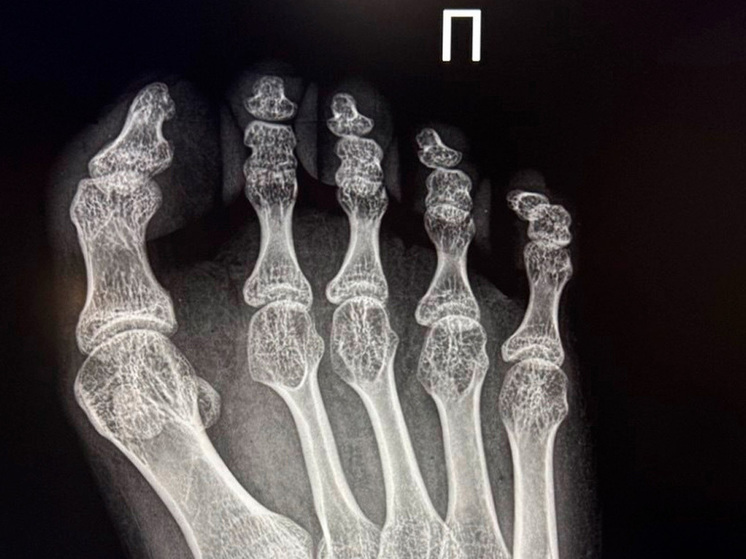

В Елецкой детской больнице Липецкой области была выполнена сложная операция для 17-летней девушки, которя страдает от детского церебрального паралича. Пациентка обратилась с жалобами на приобретенную деформацию первого пальца правой стопы 3 степени, которая причиняла ей значительные боли и затрудняла передвижение.

Заведующий травматологическим отделением, Махач Алиев, провел реконструктивное вмешательство, используя современные методики Шеде-Брандеса и Арина.